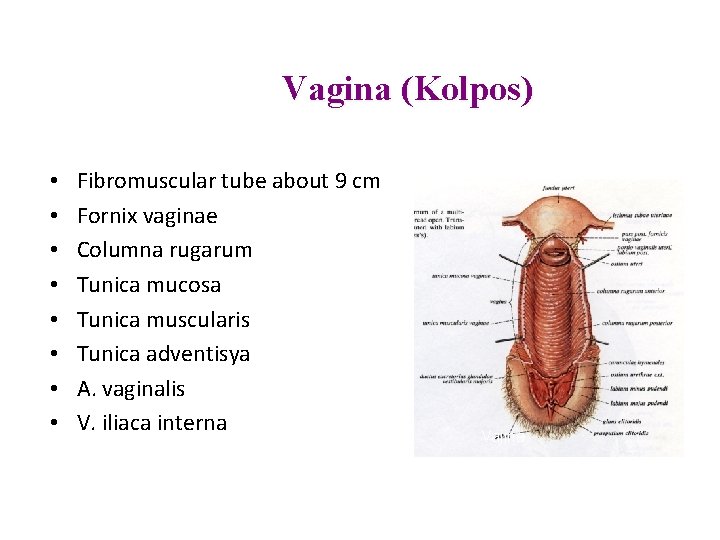

Vagina (Kolpos) • • Fibromuscular tube about 9 cm Fornix vaginae Columna rugarum Tunica mucosa Tunica muscularis Tunica adventisya A. vaginalis V. iliaca interna Vajina